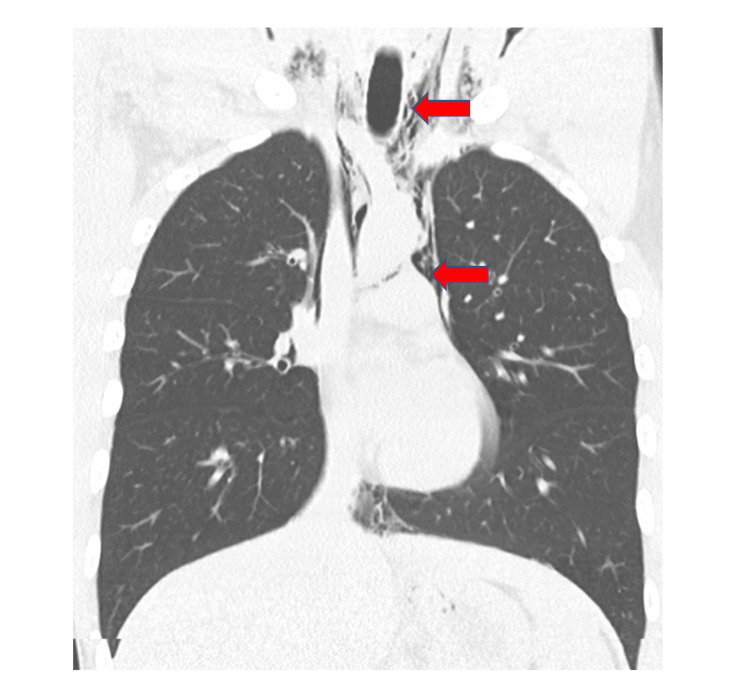

A chest x-ray revealed PM that was well seen on chest CT, and PR was seen in the neck CT (Figures 1, 2). No other findings were seen on abdominal CT. An esophageal swallowing test did not reveal any leakage. Patient was treated conservatively and given capsaicin topical cream and promethazine as needed for nausea and vomiting. Three days later, the chest x-ray did not reveal the PM; he was discharged to the care of his primary care provider (PCP) with advice to discontinue MJ. It is unclear at this time whether the patient had followed up with his PCP after discharge. It was felt that he may have had a microesophageal perforation without any significant extra-luminal damage or rupture of a peripheral bleb causing the PM and PR.

CHS has been linked to numerous cases of AKI and three suspected deaths [ref. 6]. Additionally, only two other cases of otherwise spontaneous PM in association with CHS have been reported [ref. 7]. The mechanism of PM seems likely to be a micro-tear in the esophagus that thus far has not been reported to cause Boerhaave syndrome which requires anything beyond observation. Another theory proposed to explain the association of spontaneous PM, and hyperemesis syndrome, includes the increase in thoracic pressure caused by Valsalva maneuvers during vomiting which in turn predisposes an individual to barotrauma that can rupture bullae/blebs [ref. 8]. This association of MJ smoking leading to bullae ruptures potentially causing PM and pneumothorax is more likely to be seen with concomitant tobacco smoking [ref. 9,ref. 10]. Likewise, we believe PR is another potential complication of CHS. Although located in the spinal canal, it has not been reported in association with CHS, but it has been seen in up to 9.5% of cases with PM and often presents with few symptoms specific to the diagnosis [ref. 11]. No known cases of PR have been reported with CHS. Although PR and PM are uncommonly reported with CHS, it can be seen in other conditions that cause severe vomiting through the mechanisms mentioned above.